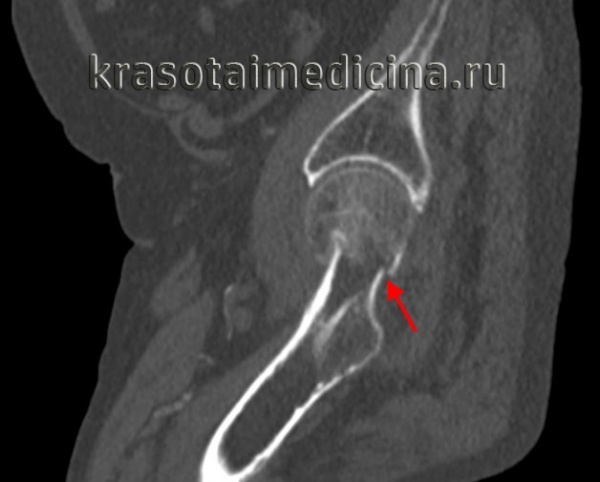

Признаки перелома головки бедренной кости

Перелом головки бедренной кости. Диагностика и лечение

Для выявления переломов этого типа достаточно, как правило, обычных рентгенограмм в прямой проекции и в проекции с наружной и внутренней ротацией бедра. Диагностике скрытых переломов часто помогают рентгенограммы в сравнительных проекциях. У всех больных с подозрением на перелом бедра должна быть тщательно изучена линия Шентона. Кроме того, при подозрении на перелом необходима оценка шеечно-диафизарного угла, который в норме составляет 120—130°. Его измеряют от точки линий пересечения, проведенных по осям диафиза и шейки бедренной кости.

Класс А: перелом головки бедренной кости

Перелом головки бедренной кости встречается редко и может проявиться в сочетании с вывихом или без какой-либо значительной деформации. Его классифицируют по двум типам на основании размера и количества фрагментов. При переломах I типа имеется один фрагмент, в то время как переломы II типа являются оскольчатыми.

Для выявления этих переломов достаточно снимков тазобедренного сустава в обычных проекциях.